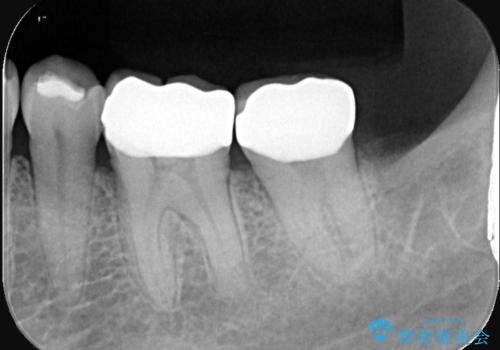

まず左下6番のヒビや弱くなった部分を除去し、セラミッククラウンが適切に装着できる形に整えました。隣接する7番についても同様に支台形成を行い、両方の歯を連続して補強する形としました。クラウンは、見た目の自然さと耐久性を兼ね備えたセラミックを選択し、咬合圧に配慮したデザインと高さ調整を丁寧に行いました。

また、ブラッシング時に不快感があった左下の親知らずは、炎症や清掃障害の原因になることから、治療前に抜歯しました。クラウン装着後は、違和感や痛みもなく、噛むときの安定感が向上。患者さんからは「しっかり噛めるようになって安心した」とご感想をいただきました。今後は定期的なメンテナンスで状態を保っていきます。